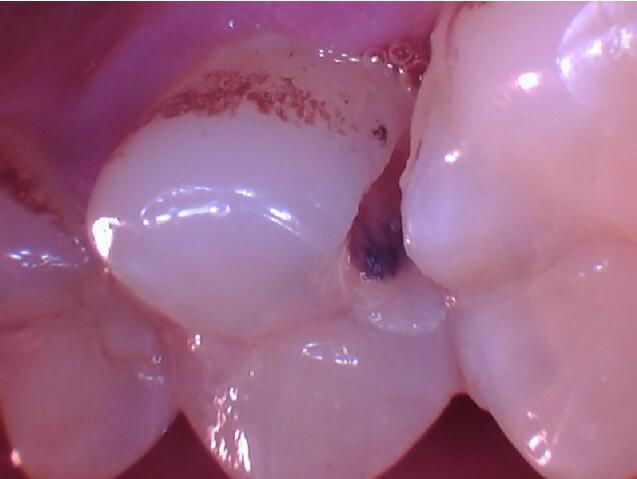

泰山口腔丨隐藏的龋病——邻面龋

顾名思义,就是龋坏在相邻两颗牙齿之间,刚开始的时候从外面不易被发现,可能只会出现吃东西时塞牙的症状。

邻面龋主要是因为牙缝难以清洁,长期菌斑食物残留,牙齿邻接面被细菌侵蚀,慢慢缺损,因为位置比较隐蔽,不易发现,当发现的时候,缺损往往比较大了。

所以,应该注意除了常规刷牙以外,可以选择用牙线清洁牙间隙并定期口腔检查